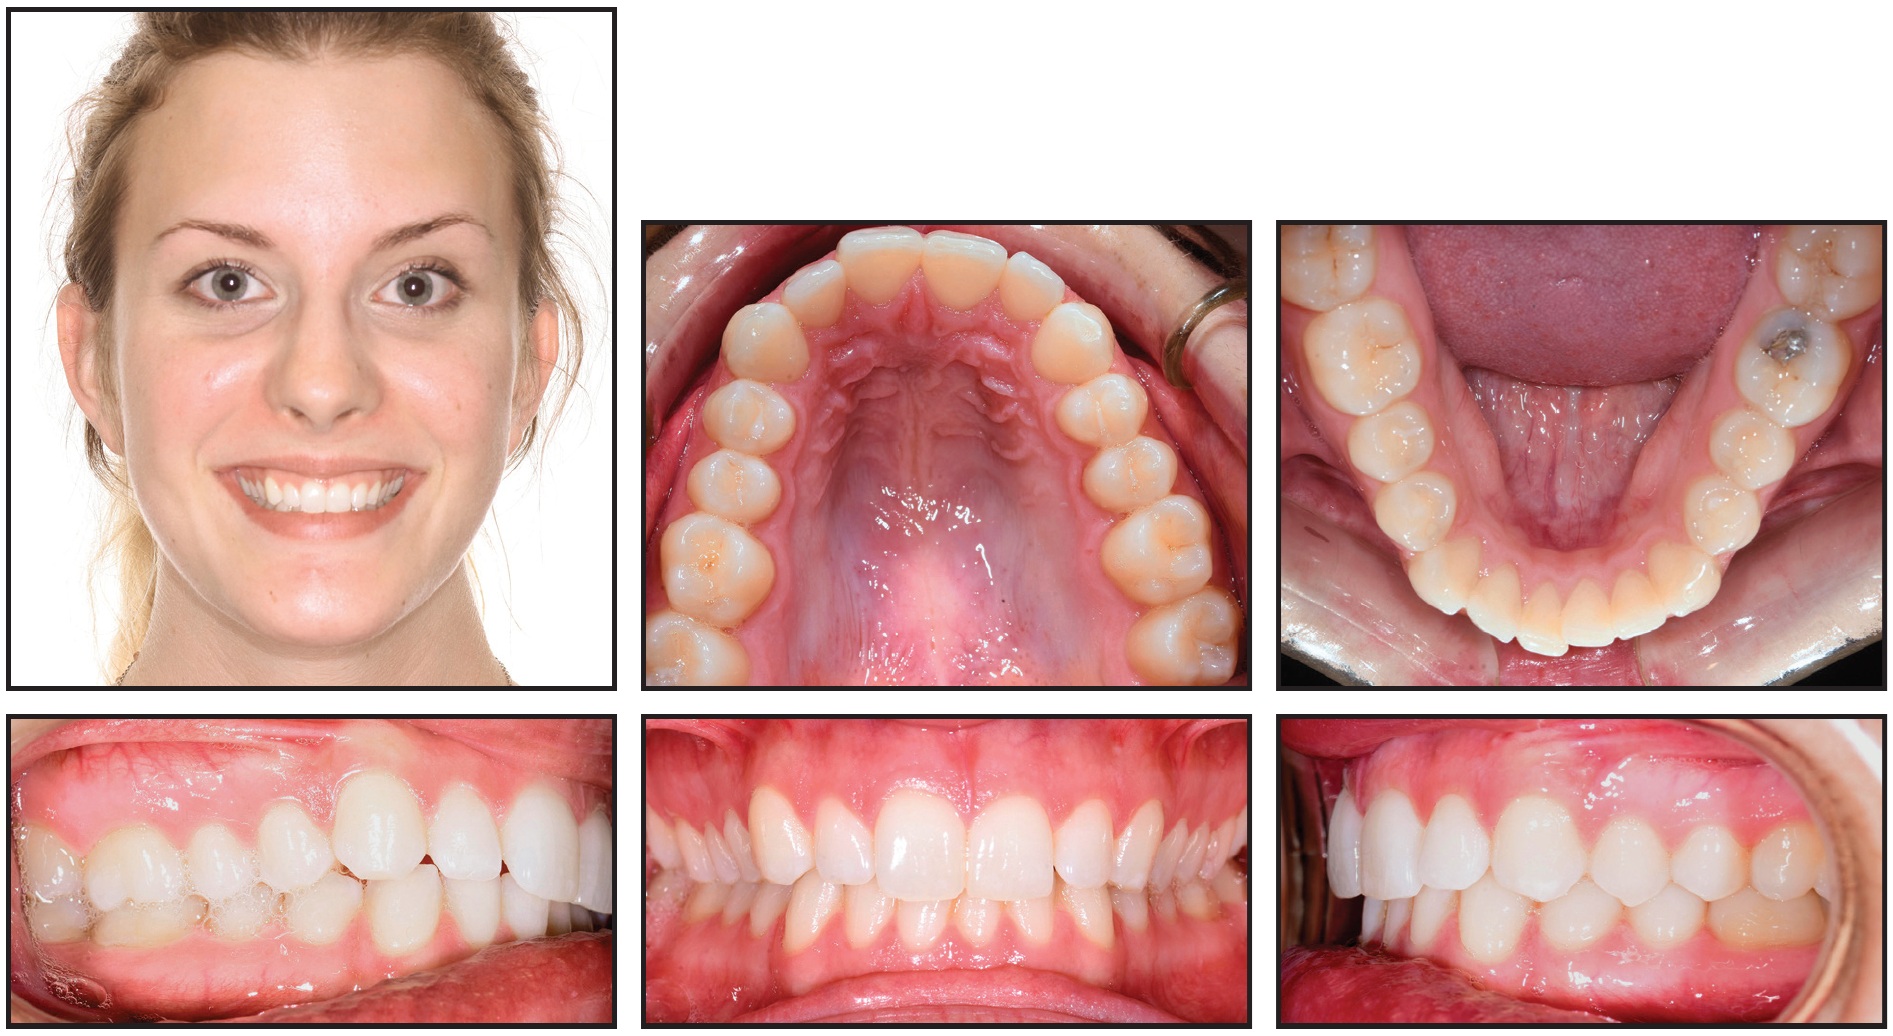

A 22-year-old female presented for treatment of minor crowding, a moderately deep bite, and narrow dental arches (Fig. 4).

Fig. 4 Case 1. 22-year-old female patient with lower midline shift, mild crowding in both arches, asymmetrical upper archform, Class I relationship on left side, and one-fourth- to one-half-unit Class II relationship on right before treatment.

Examination found a lower midline shifted 2mm to the right; mild crowding in both arches; an asymmetrical, skewed upper archform; and lips that were slightly retrusive relative to the E-line (Table 1).

A good facial profile and balance were noted, along with normal upper incisor positions and lingual tipping in the buccal segments. The molar and canine relationships were diagnosed as Class I on the left and one-fourth- to one-half-unit Class II on the right.

Treatment goals were to resolve the deep bite, broaden and enhance both arches, correct the asymmetrical maxillary archform, and finish with Class I molar and canine relationships. The estimated treatment time was 18 months.

Damon Q** brackets were bonded to all teeth in both arches: low-torque brackets on the upper and lower incisors, high-torque brackets on the lower canines, and standard brackets on all other teeth (Fig. 5). Anterior bite turbos were bonded to the lingual aspects of the upper central incisors. SmartArch .016" Copper NiTi archwires were inserted in all brackets, with no elastics worn at the start.